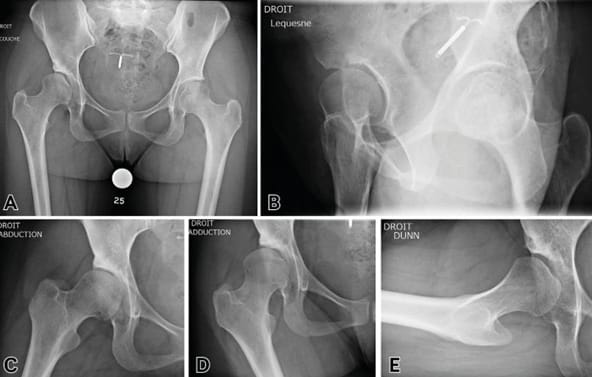

Diagnosis is confirmed by plain radiography, which should include:

- AP image of the pelvis

- False profile view of both hips (a good quality image is one taken standing and weight-bearing with the distance between the femoral heads corresponding to the diameter of one femoral head)

- Dunn view. This view has garnered support more recently due to the discovery of a frequent association between dysplasia and femoroacetabular impingement. This association seems paradoxical since dysplasia leaves the femoral head less covered which should, in theory, free the hip, but in fact retroversion of the affected hip is not uncommon, and the same goes for a cam of the anterior femur.

The following radiographic measurements are indispensable [1] Nwachukwu, B.U., et al., Arthroscopic Versus Open Treatment of Femo1. Tannast M, Hanke MS, Zheng G, Steppacher SD, Siebenrock KA. What are the radiographic reference values for acetabular under- and overcoverage? Clin Orthop Relat Res 2015 Apr;473(4):1234–46. https://doi.org/10.1007/s11999-014-4038-3 (Figure 1):

- On the AP pelvic radiograph, the VCE is normal if ≥ 25°, borderline if between 20° and 25°, and dysplastic if < 20°, with severe dysplasia if VCE is < 0° (Figure 1C).

- On the false profile view, the VCA is normal if ≥ 25°, borderline if between 20° and 25°, and dysplastic if < 20°, with severe dysplasia if VCA is < 0° (Figure 1D).

- On the AP pelvic radiograph, the acetabular index, or Sharp angle, is normal if ≤10°, borderline if between 10° and 15°, and dysplastic beyond that. Severe forms are > 25° (Figure 1E)

- The Wagner index measures femoral head coverage (or, taking the opposite perspective, the femoral head extrusion index can be used): it is normal if > 80% (Figure 1F)

- Femoral neck-shaft angle: the NSA is normal between 125° and 135° (Figure 1G)

When an intervention is being considered, a number of radiographic investigations should be performed:

- AP view of hip in abduction: indispensable to estimate the joint space if planning acetabular reorientation and/or to predict repositioning in abduction if planning a femoral varus osteotomy (Figure 3).

- AP view of hip in adduction to estimate the joint space and repositioning if a femoral valgus osteotomy is planned where there is deformity of the femoral head with medial osteophyte formation.

As it is no longer acceptable in 2024 to perform hip-preserving surgery in hip dysplasia without having contrast-enhanced CT images, the following are options:

- Arthro-CT, which is very accurate but uses more radiation than arthro-MRI (Figure 3). The advantage of arthro-CT is that labral lesions and thinning cartilage show up well. It should be preceded by a series of CT images without contrast material for 3D bone reconstruction, used to simulate the osteotomies and for the manufacture of custom cutting guides. CT can also be used to measure femoral anteversion, which may need a derotational osteotomy, as well as the AASA (anterior acetabular sector angle) and PASA (posterior acetabular sector angle).

- Arthro-MRI focuses on the functional, as it shows the painful areas of stress in the joint caused by intraosseous cysts. It is, however, less accurate than arthro-CT for imaging bone structures, which after all are the target for surgery. Unlike arthro-CT it does visualise cartilage flaps and detachment well.